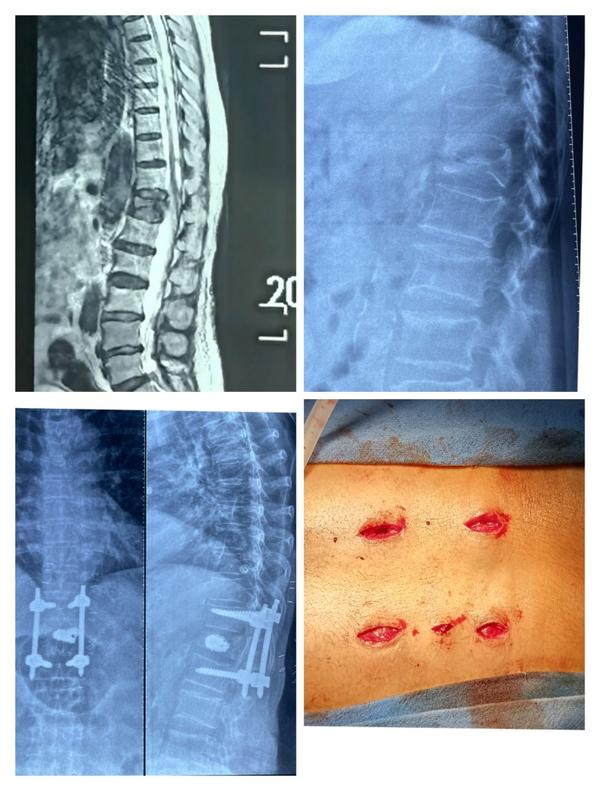

Dr Pramod Saini is an Orthopaedic Spine surgeon with expertise in Minimally Invasive Spine surgery and Endoscopic spine surgery. He is currently working as Senior Consultant with Jaypee hospital, Noida. He is an Orthopaeidic surgeon with special training in spine surgery. He specializes in treating all spine related disorders and his practice is exclusively restricted to Spinal prblems. His area o...